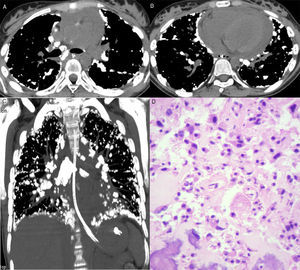

Axial computed tomography images at the level of the bronchial bifurcation (A) and lower lobes (B), and a coronal reformatted image (C) showing several calcified nodules in the subpleural regions and along fissures. Note also mediastinal lymph node calcifications and pericardial effusion. (D) Histological section showing proliferation of neoplastic cells with bone tissue formation. Note also nuclear atypia (hyperchromasia and karyomegaly) (hematoxylin and eosin stain, ×400).

A 14-year-old girl was admitted with a 30-day history of painful swelling in the left knee that had not improved with the use of analgesics and nonsteroidal anti-inflammatory drugs. An X-ray showed an aggressive osteolytic lesion in the left distal femur. Open biopsy examination revealed a proliferation of neoplastic osteoblasts producing abundant irregular osteoid matrix. The diagnosis of osteosarcoma was made. The patient started chemotherapy, but did not show good response to treatment, as the disease remained stable. Five months after diagnosis, she presented chest pain and respiratory distress. Chest computed tomography revealed several irregular calcified nodules and plaques in the subpleural regions of the lungs, as well as pericardial effusion (Fig. 1). Thoracoscopy showed numerous subpleural nodules. The histopathological diagnosis was metastatic osteosarcoma. A few days later, the patient's condition worsened, with severe dyspnea, and she died. Autopsy was performed and confirmed the lymphatic dissemination of the tumor cells.

Lung metastasis of osteosarcoma via hematogenous spread is common, but lymphangitic carcinomatosis in this tumor is very uncommon. Invasion and retrograde tumor seedlings in lymphatic and perilymphatic interstitium produce tumor spread along the interlobular septa, fissures, and pleural surfaces, with no nodular metastasis in the lungs, as seen in our patient. Involvement of lymph nodes with calcified metastasis may also be seen.1,2